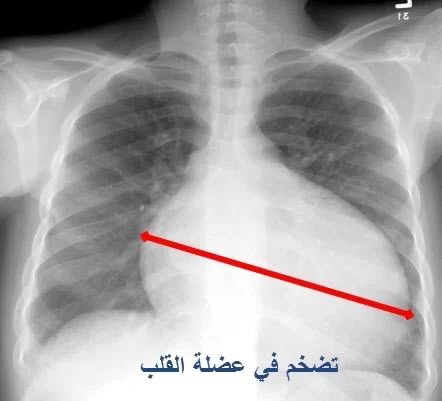

📌 | مشاركة المنطقة الوسطى (ثريد)✨.. #تضخم_القلب ( #Cardiomegaly ) 1. ما هو تضخم القلب؟ تضخم القلب هو اضطراب قلبي يتميز بزيادة حجم القلب عن الطبيعي. قد لا يظهر المرضى أي أعراض في بعض الحالات، بينما يعاني آخرون من أعراض مثل ضيق التنفس وعدم انتظام ضربات القلب.

#تضخم_القلب ( #Cardiomegaly )

1. ما هو تضخم القلب؟

تضخم القلب هو اضطراب قلبي يتميز بزيادة حجم القلب عن الطبيعي. قد لا يظهر المرضى أي أعراض في بعض الحالات، بينما يعاني آخرون من أعراض مثل ضيق التنفس وعدم انتظام ضربات القلب.